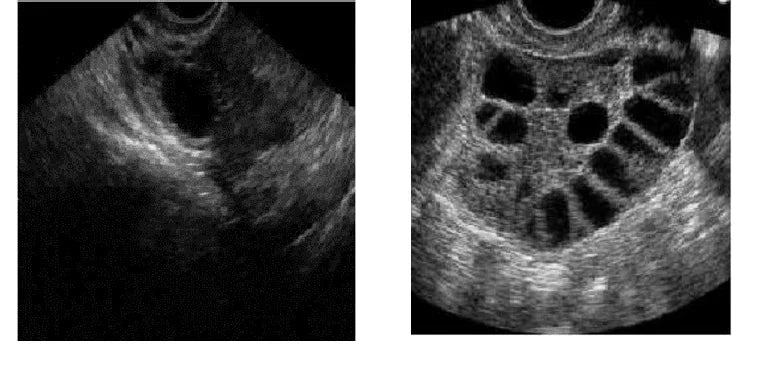

Concrètement, une AMH élevée rime souvent avec OPK (ovaires polykystiques) - Échographie de droite . Par exemple, des chercheurs ont mesuré que les femmes SOPK peuvent avoir des taux d’AMH 2 à 3 fois supérieurs à ceux de femmes sans SOPK du même âge pubmed.ncbi.nlm.nih.gov. Plus l’AMH est élevée, plus les ovaires polykystiques produisent aussi des hormones mâles en excès, signe de troubles hormonaux globalement.

Le syndrome des ovaires polykystiques (SOPK) mérite une attention particulière, étant la situation emblématique associée à un taux d’AMH haut. Dans le SOPK, rappelons-le, les ovaires contiennent un grand nombre de petits follicules (d’où le terme “polykystique”, bien que ce ne soient pas des kystes au sens pathologique). Ces follicules sécrètent tous de l’AMH, ce qui fait que les femmes OPK ont souvent une AMH bien supérieure à la normale pour leur age. C’est même parfois le premier indice : on voit une AMH étonnamment élevée chez une patiente qui consulte pour des règles irrégulières, ce qui oriente vers le diagnostic de SOPK.